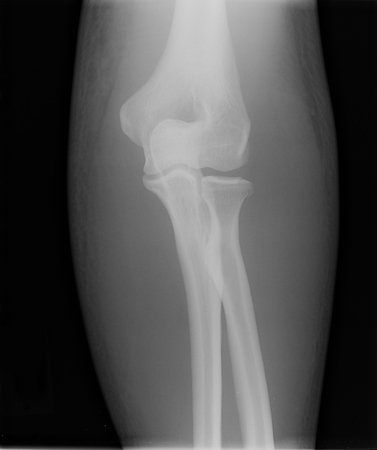

Incidência anteroposterior de radiografia de luxação do cotovelo reduzida

Acervo pessoal do Dr. Paul Novakovich